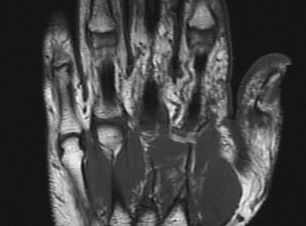

MANOS

MUÑECA